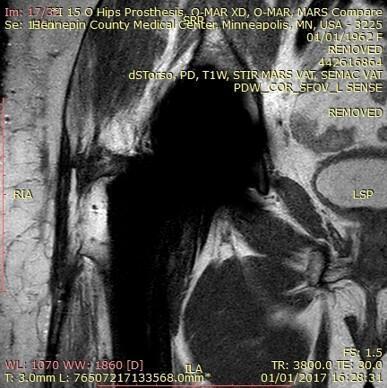

⚠️ ¿Qué son los artefactos en la resonancia asociados a prótesis?

Aunque una prótesis sea compatible, eso no garantiza que no distorsione la imagen.

Los artefactos son un efecto físico del metal sobre el campo magnético.

Como explico a mis pacientes, “aunque una prótesis sea compatible con resonancia magnética, no implica que no cree artefactos en la imagen”.

Un caso típico es el de los brackets o prótesis metálicas cercanas a la zona a estudiar: la resonancia es segura, pero puede no servir para diagnosticar correctamente.

No necesariamente. Aunque la prótesis sea compatible y no suponga un riesgo, puede producir artefactos que alteren la calidad de las imágenes y dificulten la interpretación. En mi experiencia: “aunque un dispositivo o una prótesis sea compatible con resonancia magnética, no implica que no cree artefactos en la imagen”.